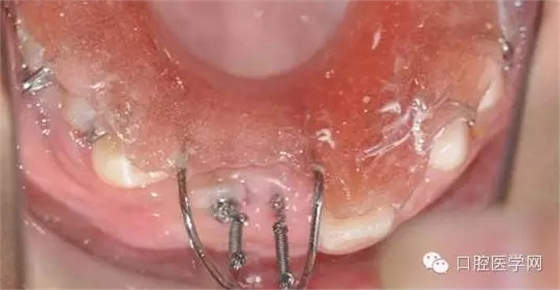

鏈狀正畸牽引裝置粘固后的口內(nèi)情況

這個(gè)鏈?zhǔn)降某?jí)好用,大力推薦。質(zhì)量很好避免了結(jié)扎絲容易斷,托槽粘結(jié)不牢的弊端。(寫到這個(gè)地方不得不聊個(gè)小橋段,上次去上海咱會(huì)淘到的這個(gè)鏈?zhǔn)焦潭ㄑb置,本來小美女說是40元一個(gè),結(jié)果我說俺常做埋伏牙,要給人家做做宣傳,10元一個(gè)就給我試用了。40元給我4個(gè),當(dāng)時(shí)那叫一個(gè)感動(dòng)呀,。。感謝生命中遇見了你。。。

縫合后,要把鏈子留到外邊: